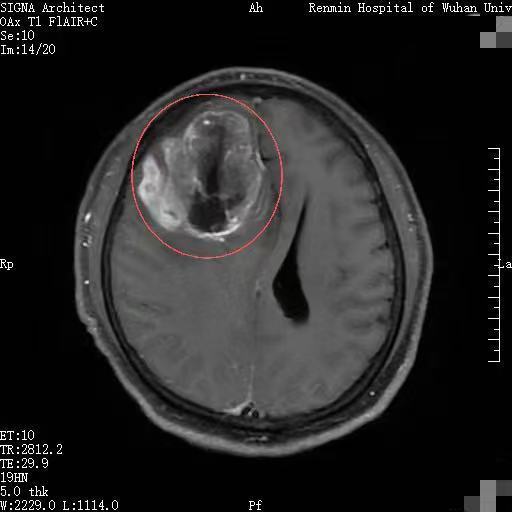

一个月前,湖北黄石市民李先生因持续半个月出现全身乏力、精神萎靡等症状,来到武汉大学人民医院东院区就诊。入住风湿免疫科后,颅脑核磁共振检查显示,其右侧额叶有一巨大占位,高度怀疑为恶性肿瘤。

更危急的是,巨大肿瘤会引发严重脑水肿,还伴有脑积水。此时,李先生颅内状况如同一颗被挤到极限的“炸弹”,随时可能危及生命。

李先生被紧急转入东院区神经外科四病区。刚转科不久,他就突发浅昏迷,一侧肢体偏瘫。急诊复查CT提示,其脑水肿较前显著加重,脑疝形成,生命体征告急。

手术难度极大。王峻教授团队如“雕刻”般彻底切除病变组织,同时小心翼翼保护负责运动、语言等重要功能的脑区及关键血管。术后,患者受压移位的脑组织逐渐复位,颅内生命通道恢复通畅。影像学复查结果显示,肿瘤切除效果满意,脑疝完全复位。